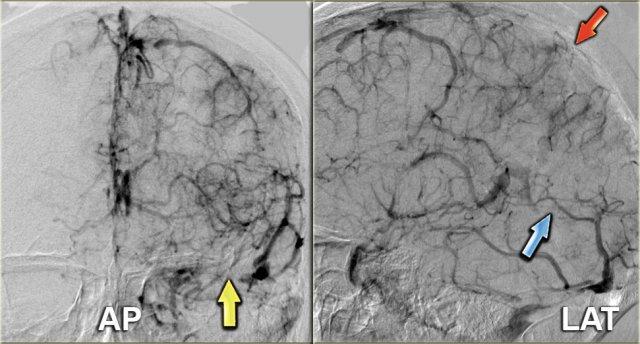

Chụp mạch số hóa xóa nền (DSA)

Chụp mạch chỉ được thực hiện trong các trường hợp nặng, khi có kế hoạch can thiệp.

Bên trái là hình ảnh của một bệnh nhân bị huyết khối tĩnh mạch, trong tình trạng hôn mê và không đáp ứng với liệu pháp chống đông.

Có huyết khối tại xoang dọc trên (mũi tên đỏ), xoang thẳng (mũi tên xanh lam) và xoang ngang – xoang sigma (mũi tên vàng).

Tiếp tục xem video về thủ thuật lấy huyết khối.

Bên trái là video về thủ thuật lấy huyết khối.